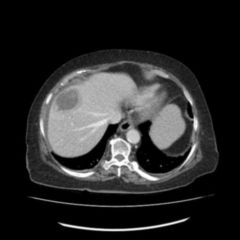

Die Symptome eines Leberabszesses sind meist hohes Fieber, Leberdruckschmerz, Übelkeit und Erbrechen, Gelbsucht und Anämie. Die Diagnose wird mittels Ultraschalluntersuchung und einer CT-Aufnahme gesichert. Die Therapie erfolgt medikamentös (durch hochdosierte Antibiotikagaben), durch eine perkutane Drainage oder durch chirurgische Entfernung der Abszesshöhle eventuell durch eine Segmentresektion. Als Komplikationen eines Leberabszesses gelten eine Sepsis oder Ruptur der Abszesshöhle mit Durchbruch in die freie Bauchhöhle und nachfolgender Bauchfellentzündung.